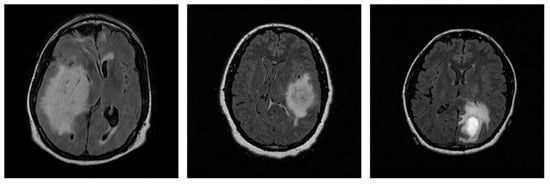

Deep learning models for three-dimensional (3D) data are increasingly used in domains such as medical imaging, object recognition, and robotics. At the same time, the use of AI in these domains is increasing, while, due to their black-box nature, the need for explainability has grown significantly. However, the lack of standardized and quantitative benchmarks for explainable artificial intelligence (XAI) in 3D data limits the reliable comparison of explanation quality. In this paper, we present a unified benchmarking framework to evaluate both intrinsic and post hoc XAI methods across three representative 3D datasets: volumetric CT scans (MosMed), voxelized CAD models (ModelNet40), and real-world point clouds (ScanObjectNN). The evaluated methods include Grad-CAM, Integrated Gradients, Saliency, Occlusion, and the intrinsic ResAttNet-3D model. We quantitatively assess explanations using the Correctness (AOPC), Completeness (AUPC), and Compactness metrics, consistently applied across all datasets. Our results show that explanation quality significantly varies across methods and domains, demonstrating that Grad-CAM and intrinsic attention performed best on medical CT scans, while gradient-based methods excelled on voxelized and point-based data. Statistical tests (Kruskal–Wallis and Mann–Whitney U) confirmed significant performance differences between methods. No single approach achieved superior results across all domains, highlighting the importance of multi-metric evaluation. This work provides a reproducible framework for standardized assessment of 3D explainability and comparative insights to guide future XAI method selection.